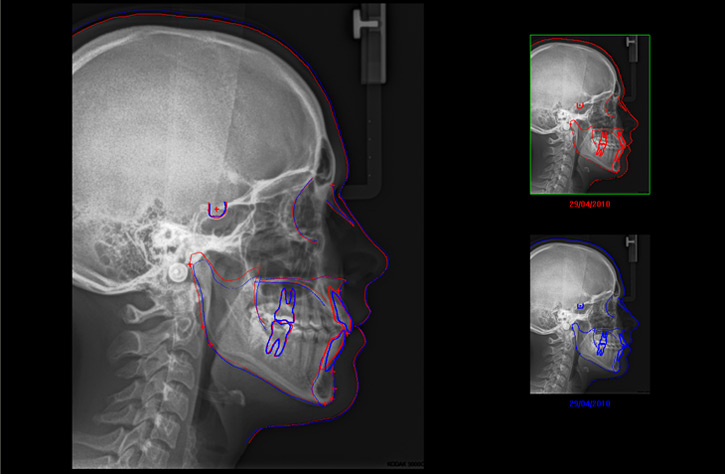

Cephalometric radiograph – an image used to gauge the cranial and facial bones. It allows to detect injuries or damages, diseases and dysmorphism within the area covered by the image. It shows soft tissues of the face, paranasal sinuses and hard palate. In orthodontic treatment it is used to assess the growth of the facial skeleton. What is more, a detailed analysis of these images helps to gauge the spatial relationships of the teeth, jaws and cranium. It is also indispensable to properly diagnose occlusal abnormalities and to plan proper treatment for individual patients. Comparing the image before and after the treatment allows to assess the treatment effectiveness. The image is indispensable to assess the progress in treatment of temporomandibular joints and relaxation of masseter muscles.

Example of cephalometric analysis: